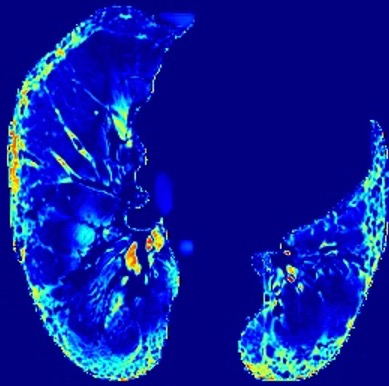

In the field of medical imaging, particularly in tasks related to early disease detection and prognosis, understanding the reasoning behind AI model predictions is imperative for assessing their reliability. Conventional explanation methods encounter challenges in identifying decisive features in medical image classifications, especially when discriminative features are subtle or not immediately evident. To address this limitation, we propose an agent model capable of generating counterfactual images that prompt different decisions when plugged into a black box model. By employing this agent model, we can uncover influential image patterns that impact the black model's final predictions. Through our methodology, we efficiently identify features that influence decisions of the deep black box. We validated our approach in the rigorous domain of medical prognosis tasks, showcasing its efficacy and potential to enhance the reliability of deep learning models in medical image classification compared to existing interpretation methods. The code will be publicly available at https://github.com/ayanglab/DiffExplainer.